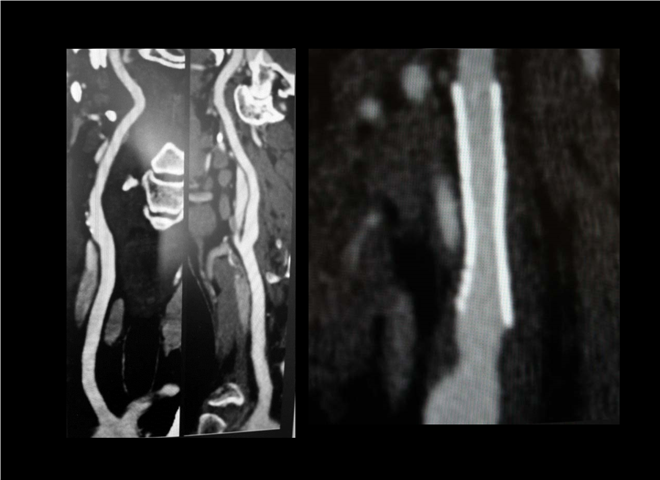

13_CT增强扫描